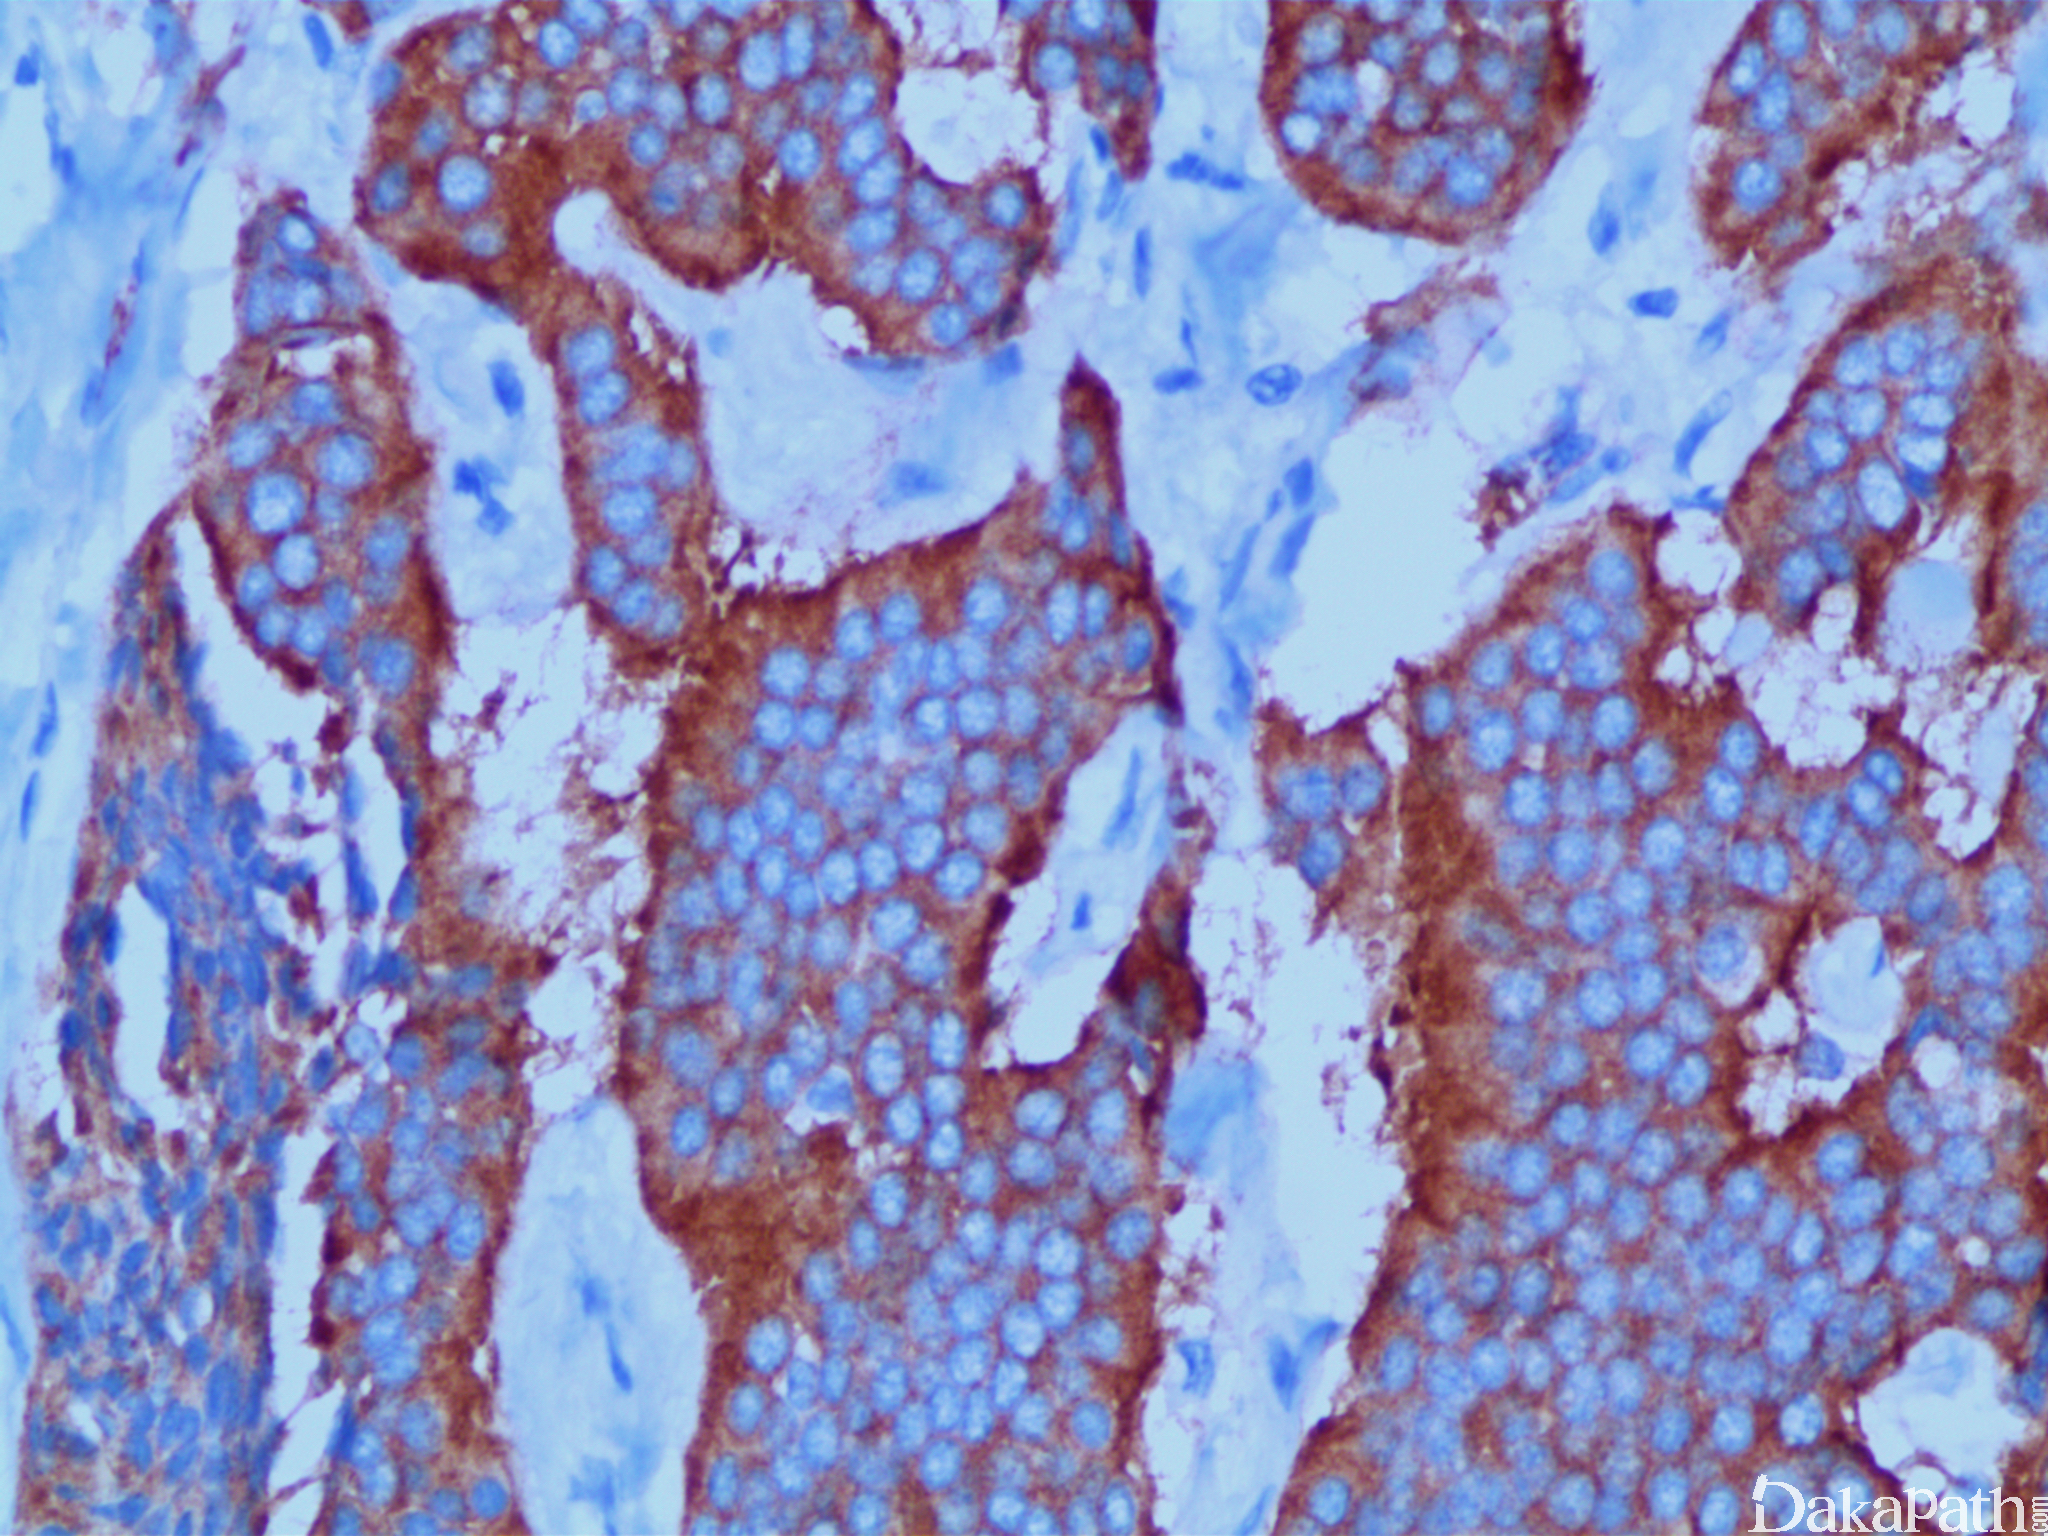

组织学上呈单一细胞巢状、条状及缎带状排列,可出现腺泡状或腺样结构,染色质椒盐样,直肠部位有时表面伴腺瘤形成。核分裂像<2 个/10HPF,Ki67 指数小于等于 2%。

免疫组织化学染色:

synaptophysin、chromogranin 及 CD56 均阳性。AE1/AE3 常阳性。